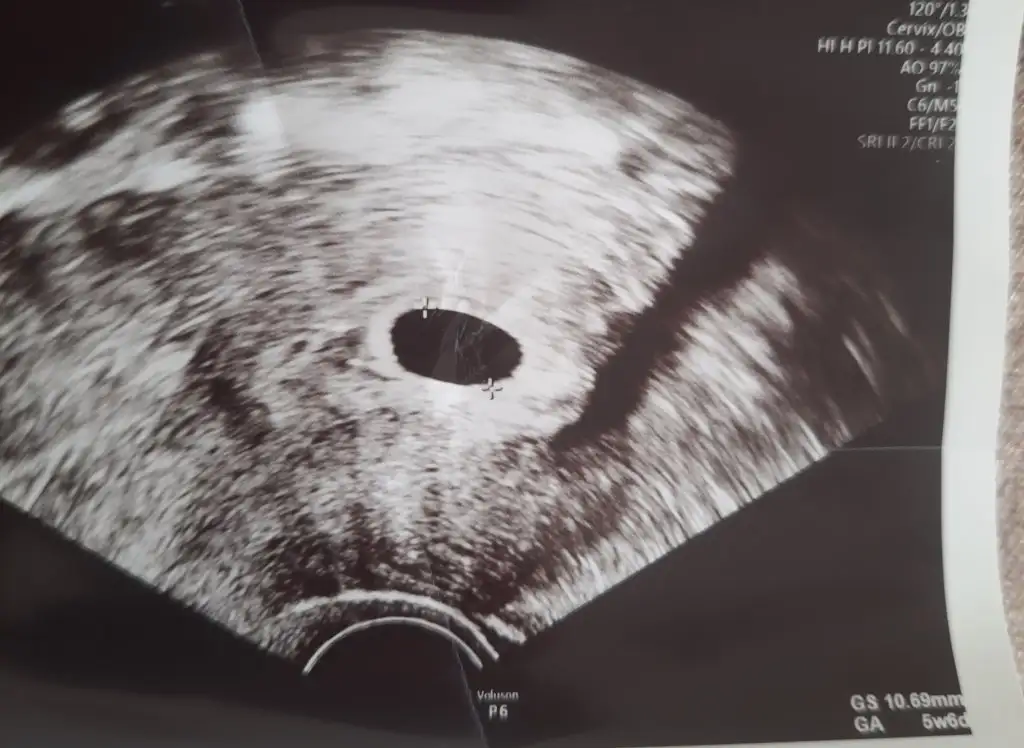

Cumartesi günü randevum var 6+1 oluyoruz o zaman kalp atisi alırız inşallah yabana göre 6+4 ama keseye göre 6+1 inşallah bu ay Eylül anneleri olursunuz ikiniz de kuzum ya. Valla dualarımda eksik değilsiniz

7.haftaya kadar beklenebilir canım geç döllenme olabilir bekleyin şu anda görmek için erken olabilirKızlar. Biz yine boş gebelik şüphesiyle eve döndükpazar gittiğimde karından bakmisti doktor 5+2 demişti. Kendi doktorum vajinal baktı 5+6 şuan içi boş dedi. Haftaya cuma gel tekrar bakalım dedi moraller sıfır